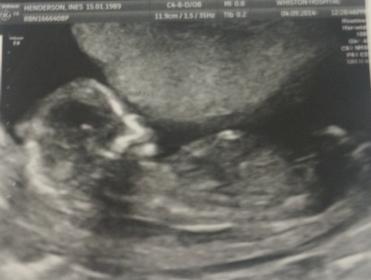

Finally had my dating scan :). Would love some gender guesses!

At nearly 15 weeks they wouldn't tell you the gender? I'm not seeing anything particularly boyish there (at 15 weeks you'd see a turtle from the side) but it's not a typical girl nub/clitoris shot either. Any other pics?

No, I'm in the UK and unless you go private it's very unlikely you're told gender before 20 weeks. Also don't get more than 1 picture :(. We've got 2 boys already so I'm very much expecting another one :)!